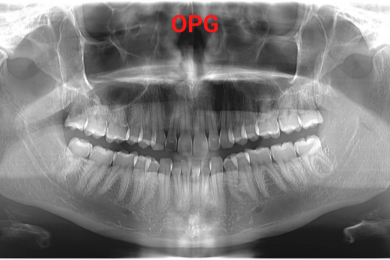

- رادیوگرافی: تصویربرداری پانورامیک ((OPG و لترال سفالومتریک برای بررسی دقیقتر وضعیت دندانها، ریشه ها، زوایای فک و صورت، دندانهای نهفته یا ناهنجاریهای استخوانی انجام میشود.